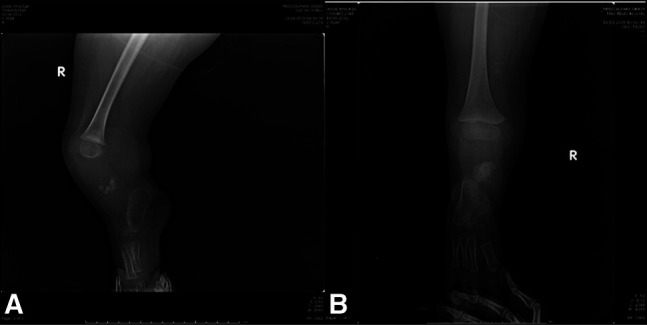

胫骨偏瘫是一种罕见的先天性缺陷,具有挑战性的治疗。适当的护理因许多亚型和相关的膝关节和踝关节畸形而异。截肢仍然是最被接受的治疗方法,但通常不被家庭所接受。因此,也提供了其他重建方案。在以下两个病例中,我们通过踝关节融合而不是截肢进行了膝关节重建。这项技术在以前的文献中没有报道过,被命名为Cabukoglu重建技术或cruris成形术。

Tibial hemimelia is a rare congenital deficiency that is challenging to treat. Appropriate care varies due to the many subtypes and associated knee and ankle deformities. Amputation is still the most accepted treatment, but it is not generally preferred by families. Consequently, other reconstruction options have been made available as well. In the following two cases, we performed knee joint reconstruction by fusion of the ankle joint instead of amputation. This technique has not been reported before in the literature and has been named as Cabukoglu reconstruction technique or cruris plasty.